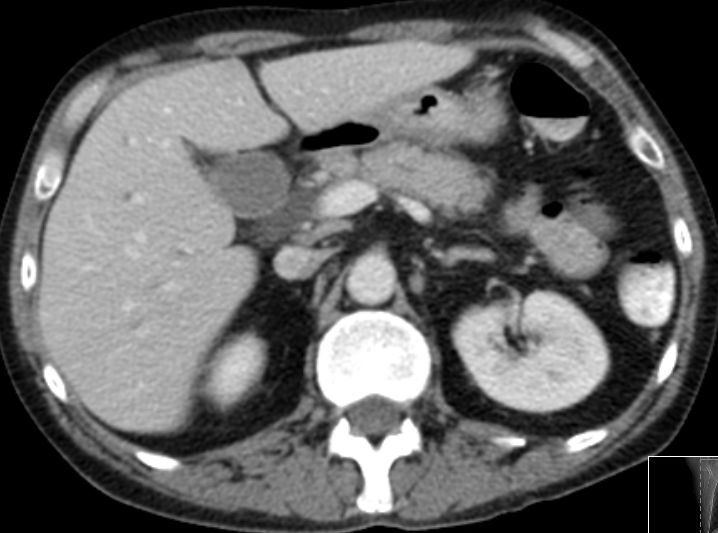

| Leber - Metastasierung | ![]() |

48-jähriger Mann mit hepatisch metastasiertem Pankreaskopf-Karzinom.

Histologische Sicherung vor 6 Monaten: schlecht differenziertes Adenokarzinom. Chemotherapie: FOLFOXIRI. Restaging: Progress. Leber mit Metastasen durchsetzt.![]() |